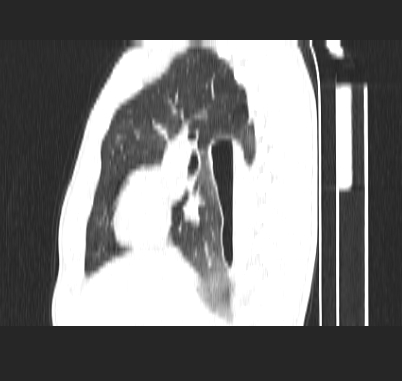

标题: CT19170:男 24岁,胸部外伤一周行CT检查 [打印本页]

男 24岁,胸部外伤一周行ct检查 未传纵隔窗

结合病史考虑肺挫伤后所致的肺气囊表现

结合临床考虑为右肺下叶背段撕裂伤。

首先考虑肺裂伤形成的液气囊肿.纵膈胸膜包裹性的液气胸可能性小,病变主要在肺内.

支持外伤性肺气囊。

肺撕裂伤液气囊形成

考虑外伤肺撕裂致右肺下叶纵隔胸膜下液气囊肿。

结合临床考虑为右肺下叶背段撕裂伤后形成局限性包裹性的液气胸。